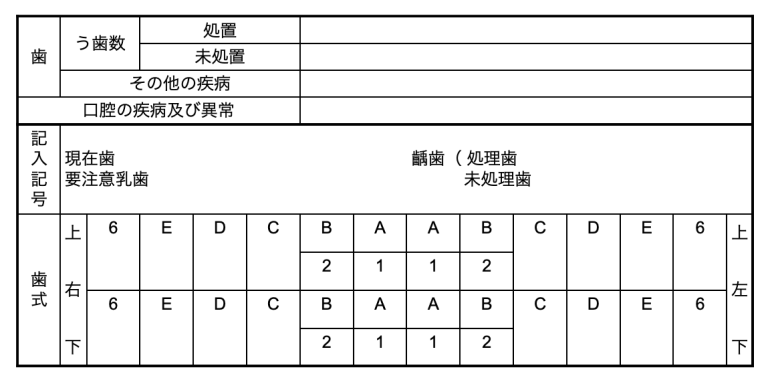

歯式について

歯科健診票

| 健全歯(現在歯) | /or未記入 |

う蝕またはう蝕処置が認められない歯 |

|---|---|---|

| 要観察歯 | CO |

主として視診にてう窩は認められないが、う蝕の初期症状(病変)を疑わしめる所見がある歯経過観察を行うことが適当と判断される歯 |

| 予防填塞歯 | シ |

う蝕予防のため、小窩裂溝に合成樹脂や歯科用セメントを填塞している歯 |

| 未処置歯 | C |

歯質に実質欠損が認められる歯。治療中の歯。処置歯にう蝕が再発している歯。 |

| 処置歯 | ◯ |

う蝕処置が完了している歯 |

| 喪失歯 | △ |

う蝕や外傷などにより抜去、脱落した歯 |

| 要注意乳歯 | ✖️ |

生え変わりが近づいてグラつきが起き、注意が必要な歯 |

| 癒合歯 | 癒合 |

2本の歯が癒合(着)している歯 |

| 過剰歯 | 過剰 |

先天的に過剰に萌出している歯 |

| 先天性欠如歯 | 先欠 |

先天的に欠如している(疑いのある)歯 |